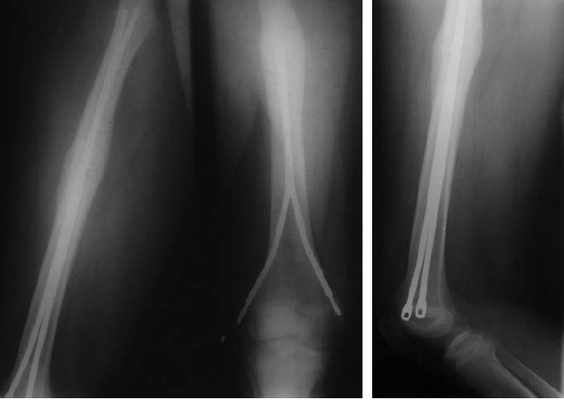

Рис. 1. Перед удалением металлоконструкций

На момент выписки из стационара после удаления металлоконструкций функция конечности была восстановлена в полном объеме, осевых деформаций не отмечалось. Через 1,5 года после травмы родители ребенка начали отмечать формирование деформации коленного сустава. Ребенок жалоб не предъявлял. Пациентка была взята на контроль с динамическим наблюдением. В течение последующих 2 лет отмечалось постепенное прогрессирование деформации с формированием genu recurvatum и укорочением конечности до 2 см (рис. 2 — 2,5 года после травмы; рис. 3 — 3,5 года после травмы).

Рис. 2. 2,5 года после травмы

Рис. 3. 3,5 года после травмы